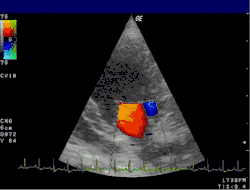

Цветовое доплеровское картирование (ЦДК)

Основано на кодировании в цвете значения доплеровского сдвига излучаемой частоты. Методика обеспечивает прямую визуализацию потоков крови в сердце и в относительно крупных сосудах. Красный цвет соответствует потоку, идущему в сторону датчика, синий — от датчика. Темные оттенки этих цветов соответствуют низким скоростям, светлые оттенки — высоким. Недостаток: невозможность получения изображения мелких кровеносных сосудов с маленькой скоростью кровотока. Достоинства: позволяет оценивать как морфологическое состояние сосудов, так и состояние кровотока по ним.

Кардиология, сосудистая и кардиохирургия

Эхокардиография (ЭхоКГ) — это ультразвуковая диагностика заболеваний сердца. В этом исследовании оцениваются размеры сердца и его отдельных структур (желудочки, предсердия, межжелудочковая перегородка, толщина миокарда желудочков, предсердий и т. д.), наличие и объём жидкости в полости перикарда, состояние клапанов сердца, а также, в доплеровском режиме, кровоток в сердце и магистральных сосудах. С помощью специальных расчетов и измерений эхокардиография позволяет определять массу миокарда, сократительную способность сердца (фракцию выброса, сердечный выброс и др.). Обычно ЭхоКГ проводится через грудную клетку (трансторакально), также существует чреспищеводная ЭхоКГ (ЧП-ЭхоКГ), когда специальный эндоскопический датчик помещается в пищевод. ЧП-ЭхоКГ позволяет лучше рассмотреть сердце, так как датчик располагается к сердцу ближе, чем при обычной ЭхоКГ и поэтому становится возможным использовать датчик с более высокой частотой ультразвука, что повышает разрешающую способность изображения. Также существуют специальные высокочастотные интраоперационные датчики, которые помогают во время операций на сердце.

4D-ЭхоКГ представленная на изображении, позволяет получать живое 3D-изображение сердца, то есть в реальном времени, что может быть также полезно, для проведения данной методики требуется специальный 4D-датчик.